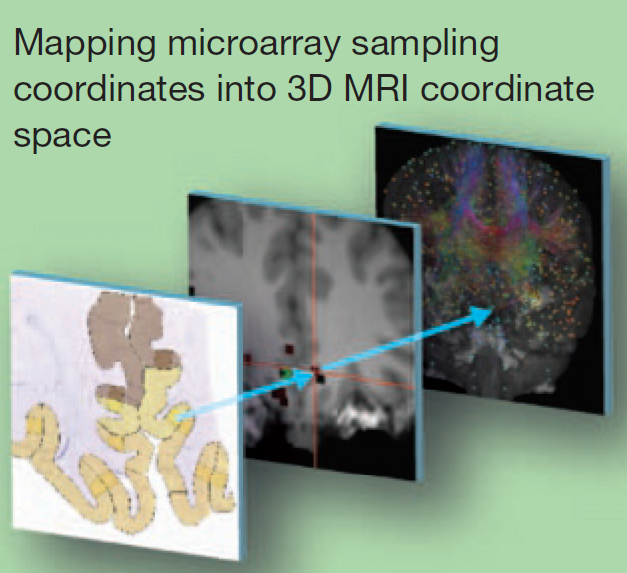

最后将基因表达的数据map到MRI的空间中